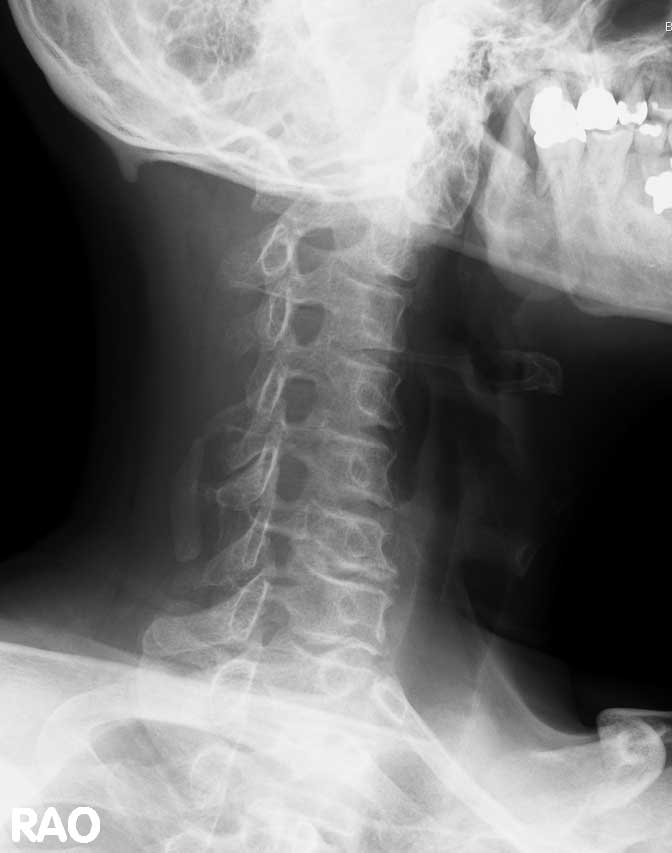

病院にて撮影されたレントゲン画像にてC6後方変位を確認し、C6のみの矯正を行いました。1か月間に約8回の施術を行い、症状の改善が見られました。さらに約1か月間に4回の矯正の施術を行った結果、ほとんど症状が消失されました。